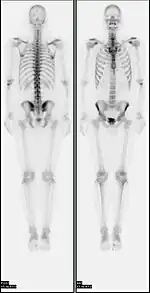

![]() A nuclear medicine whole-body bone scan. The nuclear medicine whole-body bone scan is generally used in evaluations of various bone-related pathology, such as for bone pain, stress fracture, nonmalignant bone lesions, bone infections, or the spread of cancer to the bone. | |

A bone scan or bone scintigraphy /sɪnˈtɪɡrəfi/ is a nuclear medicine imaging technique of the bone. It can help diagnose a number of bone conditions, including cancer of the bone or metastasis, location of bone inflammation and fractures (that may not be visible in traditional X-ray images), and bone infection (osteomyelitis).[1]

Nuclear medicine provides functional imaging and allows visualisation of bone metabolism or bone remodeling, which most other imaging techniques (such as X-ray computed tomography, CT) cannot.[2][3] Bone scintigraphy competes with positron emission tomography (PET) for imaging of abnormal metabolism in bones, but is considerably less expensive.[4] Bone scintigraphy has higher sensitivity but lower specificity than CT or MRI for diagnosis of scaphoid fractures following negative plain radiography.[5]